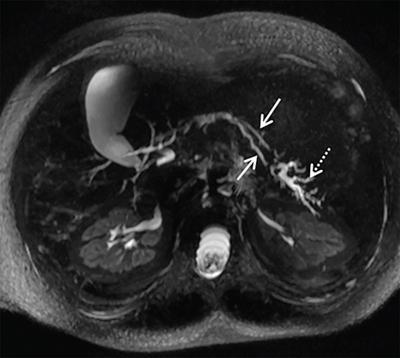

• On MRCP or endoscopic retrograde cholangiopancreatography (ERCP), it manifests as duplication of the major duct in the body or tail of the pancreas.

Image

Axial 3D MRCP image depicting bifid pancreatic duct in body region of pancreas (arrows) with changes of moderate to severe pancreatitis in the tail region (dashed arrow) in the form of dilated side duct branches.